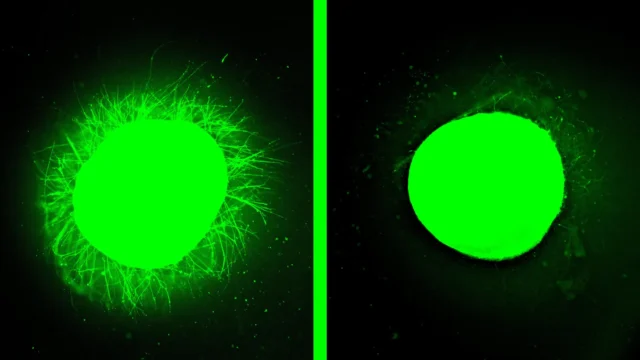

Quando organoides danificados foram tratados com “moléculas dançantes” – uma terapia que restaurou o movimento e regenerou o tecido em um estudo anterior com animais – os resultados foram dramáticos. O tecido danificado produziu um crescimento significativo de neuritos, o que significa que as longas extensões que permitem a comunicação dos neurônios começaram a crescer novamente. O tecido semelhante a uma cicatriz foi bastante reduzido. As descobertas apoiam a ideia de que esta terapia, que recentemente recebeu aprovação da Food and Drug Administration (FDA) dos EUA, poderia melhorar a recuperação de pessoas com lesões na medula espinhal.

“Um dos aspectos mais interessantes dos organoides é que podemos usá-los para testar novas terapias em tecidos humanos”, disse Samuel I. Stapp, da Northwestern, autor sênior do estudo e inventor das moléculas dançantes. “Esta é a única maneira de atingir esse objetivo, além dos ensaios clínicos. Decidimos desenvolver dois modelos de lesão diferentes em um organoide da medula espinhal humana e testar nossa terapia para ver se os resultados eram semelhantes aos que havíamos visto anteriormente em um modelo animal. Depois de aplicar nossa terapia, a cicatriz glial desapareceu significativamente e tornou-se quase invisível, e vimos neurites crescendo, lembrando a regeneração axonal que observamos em animais. Esta é a confirmação de que nossa terapia tem uma boa chance de funcionar em humanos.”

Depois de ser tratado com as moléculas dançantes, a estrutura de nanofibra semelhante a um gel reduziu a inflamação, reduziu as cicatrizes gliais, estimulou a extensão de neurites e encorajou os neurônios a crescerem em padrões organizados.

Stapp atribui a eficácia da terapia ao movimento supramolecular, ou seja, a capacidade das moléculas de se moverem rapidamente e até mesmo se separarem brevemente da malha de nanofibras. Experimentos em organoides saudáveis confirmaram essa ideia.

“Antes mesmo de desenvolvermos um modelo de lesão, testamos a terapia em um organoide saudável”, disse ele. “As moléculas dançantes liberaram todas essas longas neurites na superfície do organoide, mas quando usamos moléculas que tinham menos ou nenhum movimento, não vimos nada. Essa diferença foi muito impressionante.”